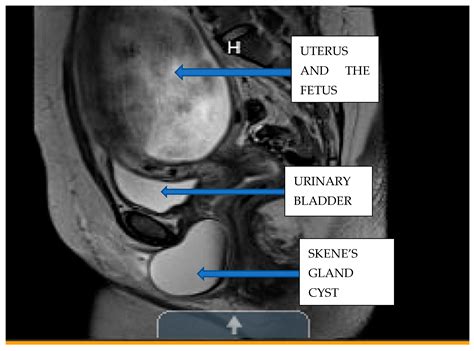

• Imaging Studies: Ultrasound, MRI, and CT scans are commonly used to visualize the cyst and determine its location and size.

Imaging studies are particularly crucial in differentiating Gartner’s Duct Cyst from other types of cysts or tumors in the pelvic region.